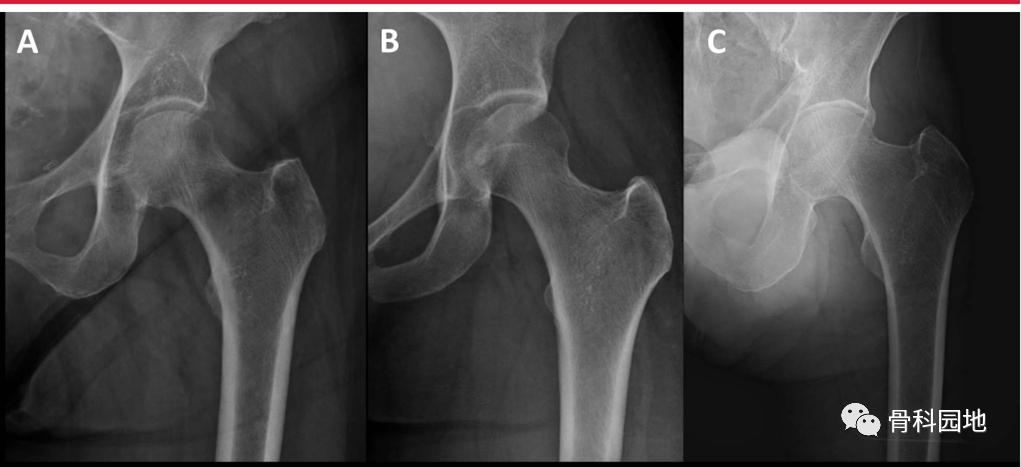

专门的髋部x线片是评估骨折形态的必要条件。虽然大转子尖端与股骨头中心之间的关系通常是共面的,但正位骨盆或对侧髋关节x线片可以帮助评估天然解剖结构和潜在的髋外翻(coxa valga )或者髋内翻(coxa vara) (下图A正常颈干角,B髋外翻,C髋内翻)